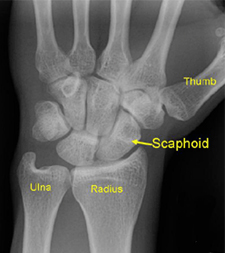

Scaphoid (wrist bone) Fracture

The scaphoid or navicular bone is the most commonly fractured wrist bone. It is usually the result of a fall onto the outstretched hand. Often, these fractures are initially missed on routine x-rays or ignored by the patient as a “sprain.” If not treated appropriately, a scaphoid fracture may not heal, resulting in eventual collapse and arthritis of the wrist many years later. The scaphoid bone takes longer than most bones to heal. Sometimes surgery is recommended to place a screw across the fracture for better healing.